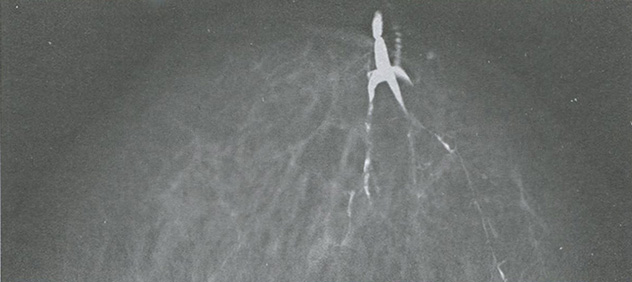

Рис. 3.1. Непальпируемое образование в виде узла (а); скопления микрокальцинатов размером более 50 микрон (б); локальной тяжистой перестройки структуры (в); непальпируемое образование — цистаденопапиллома (г)

Рис. 3.2. Дуктограмма. Внутри протока — злокачественное новообразование размером до 3 мм